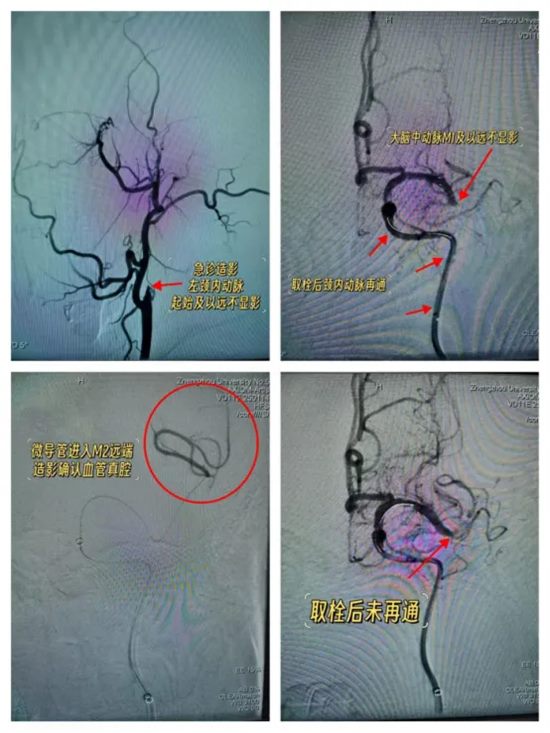

马建主任、周少龙副主任带领神经外科三病区脑血管病介入团队,率先为患者实施脑血管造影。结果清晰显示:患者左侧颈内动脉及大脑中动脉闭塞。

结合造影图像及患者病情,考虑为颈内动脉串联闭塞——这是急性缺血性脑卒中当中较为复杂、极具挑战性的亚型,治疗难度大、风险高,对术者的技术水平和决策能力提出了极高要求。

经过35分钟的紧张奋战,手术取得阶段性成功——首次开通患者左侧颈内动脉,脑血管造影显示颈内动脉血流通畅!

然而,大脑中动脉M1末端及以远仍不显影。团队尝试开通,支架+负压抽吸取栓后造影——大脑中动脉M1末端及以远仍不显影!

按照常规思路,需继续实施取栓操作,开通大脑中动脉。但此时,马建主任、周少龙副主任没有盲目推进,而是冷静下来,反复回看造影图像。

他们发现:大脑前动脉向大脑中动脉供血区域有代偿。

意味着:大脑中动脉可能并非急性闭塞。此时即便不开通,凭借侧支循环的代偿作用,也不会造成大面积脑梗死,患者的生命安全已基本得到保障。

反之,若强行继续取栓,不仅难以达到预期效果,还可能导致脑出血等致命并发症——得不偿失。

经过审慎评估和科学研判,马建主任与周少龙副主任果断决定:终止手术。

复查头颅CT印证诊断:左侧颈内动脉急性栓塞、大脑中动脉慢性闭塞